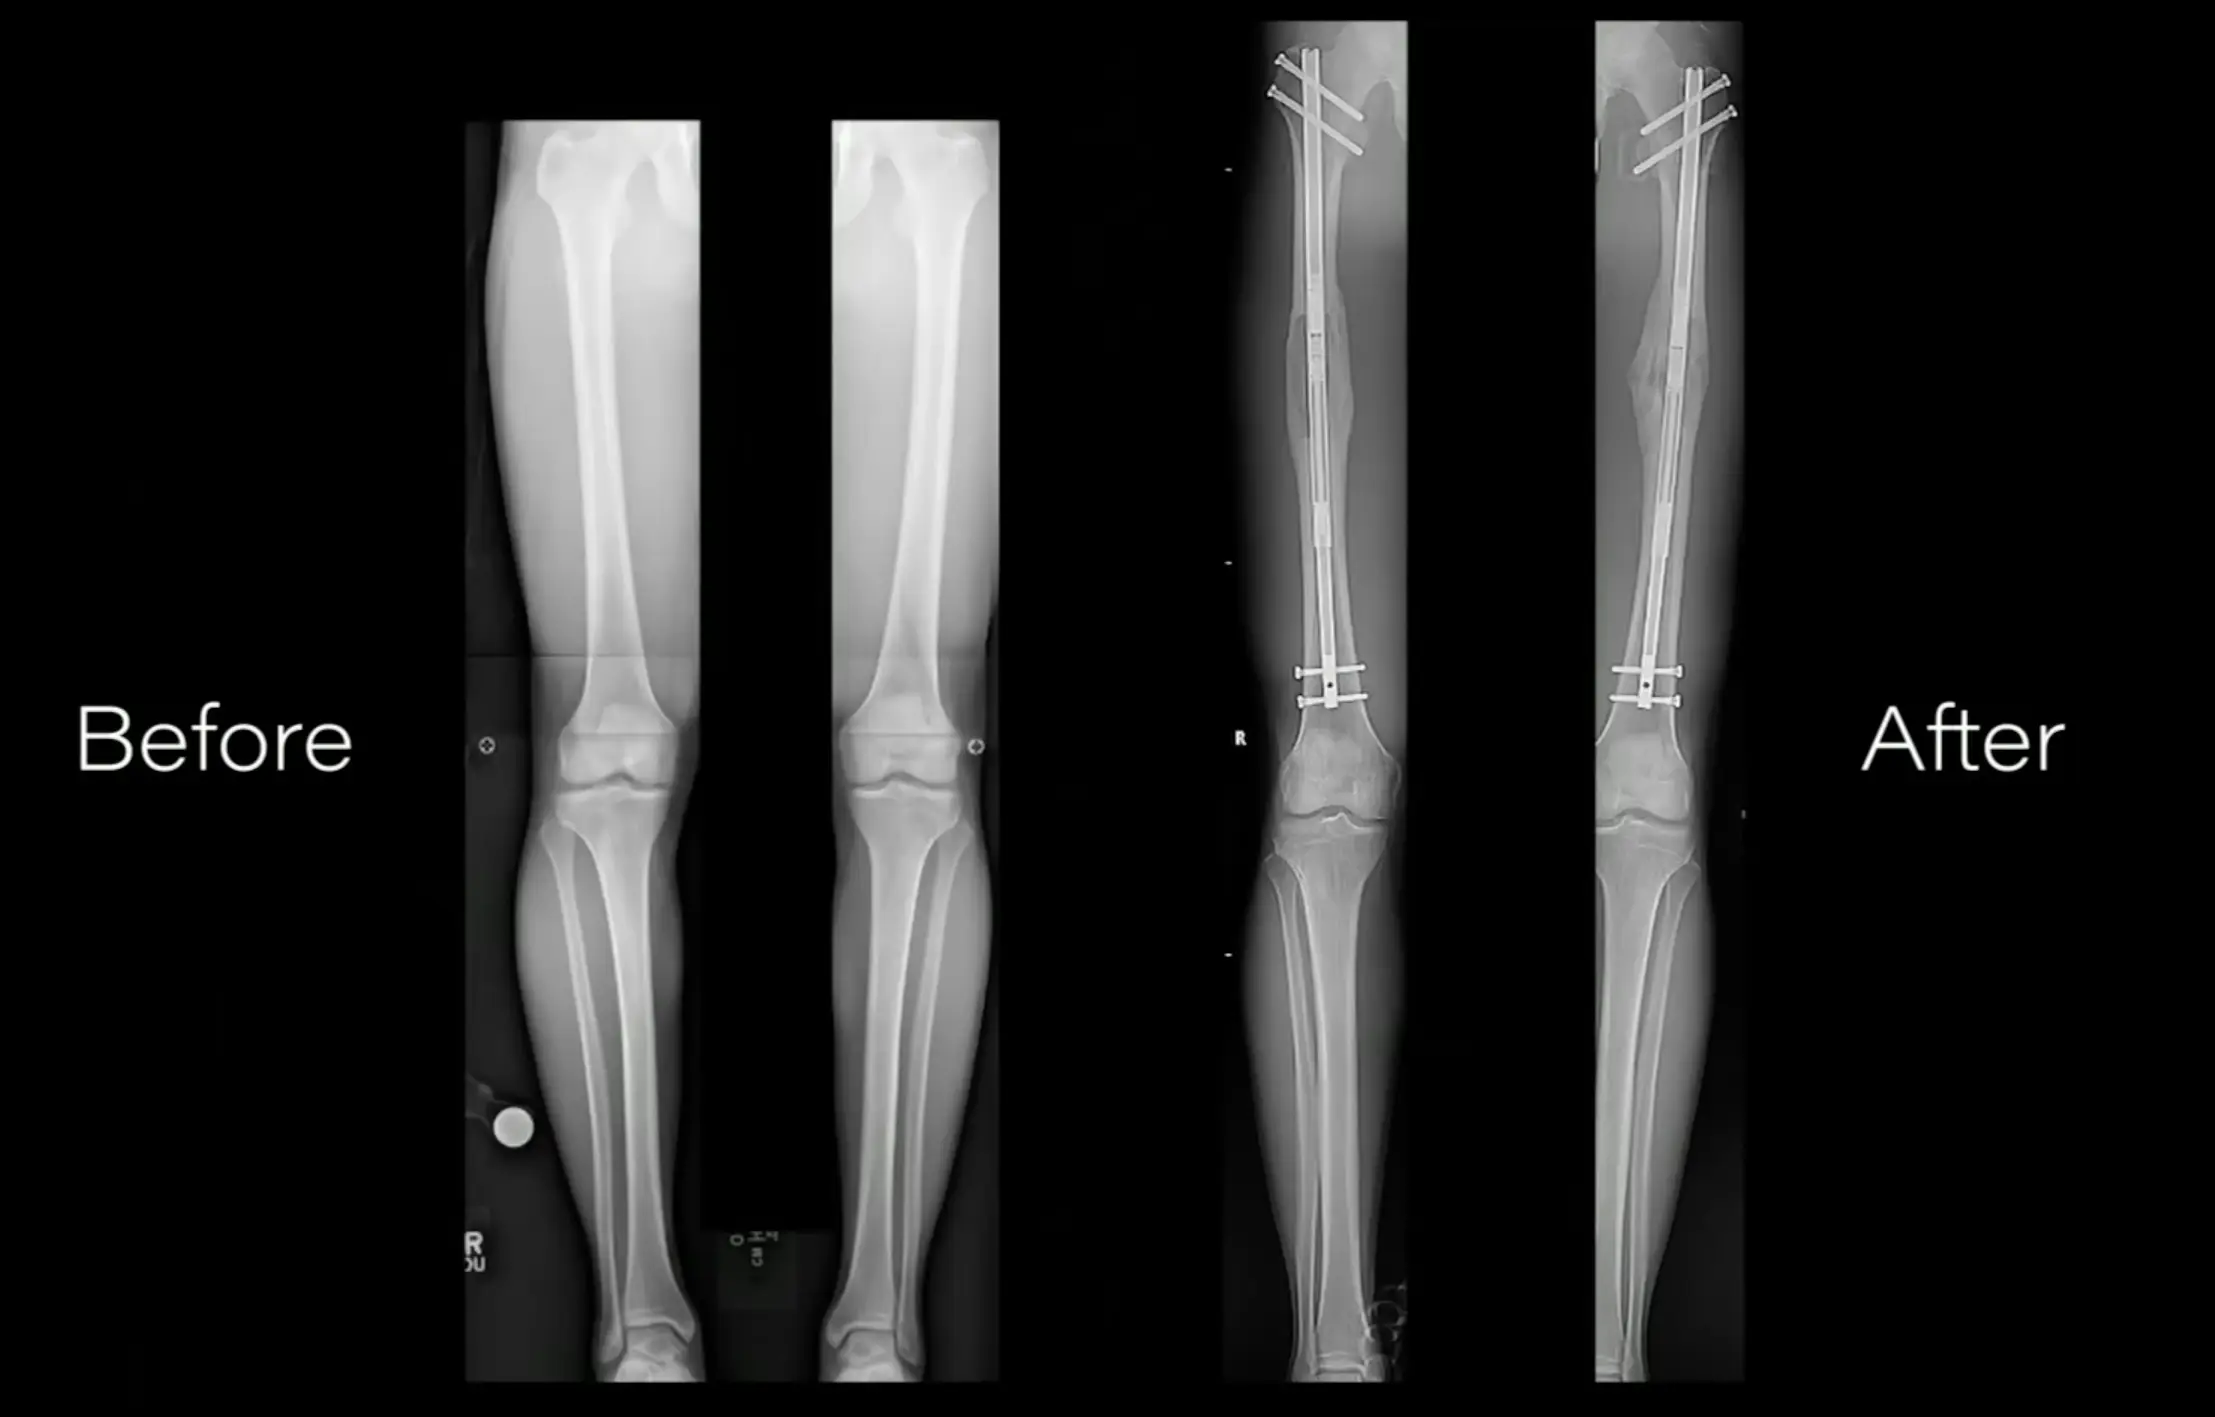

Things get off to a strong start when the bones in the thighs are broken. A series of metal pins and braces are then implanted to the area around the break with a little screw sticking out.

Over the next few weeks the patient has to turn the screw a set amount each day. This gradually stretches out the leg as the bone is healing.

Then, once you have reached the desired length, you allow the leg to fully heal and begin rehabilitation with a physiotherapist so you can learn to get around with your new height.

It might sound far-fetched, but the procedure can result in gaining several inches in height.